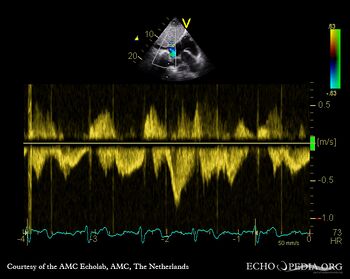

Pulsed-wave signal of hepatic venous flow: systolic flow reversal